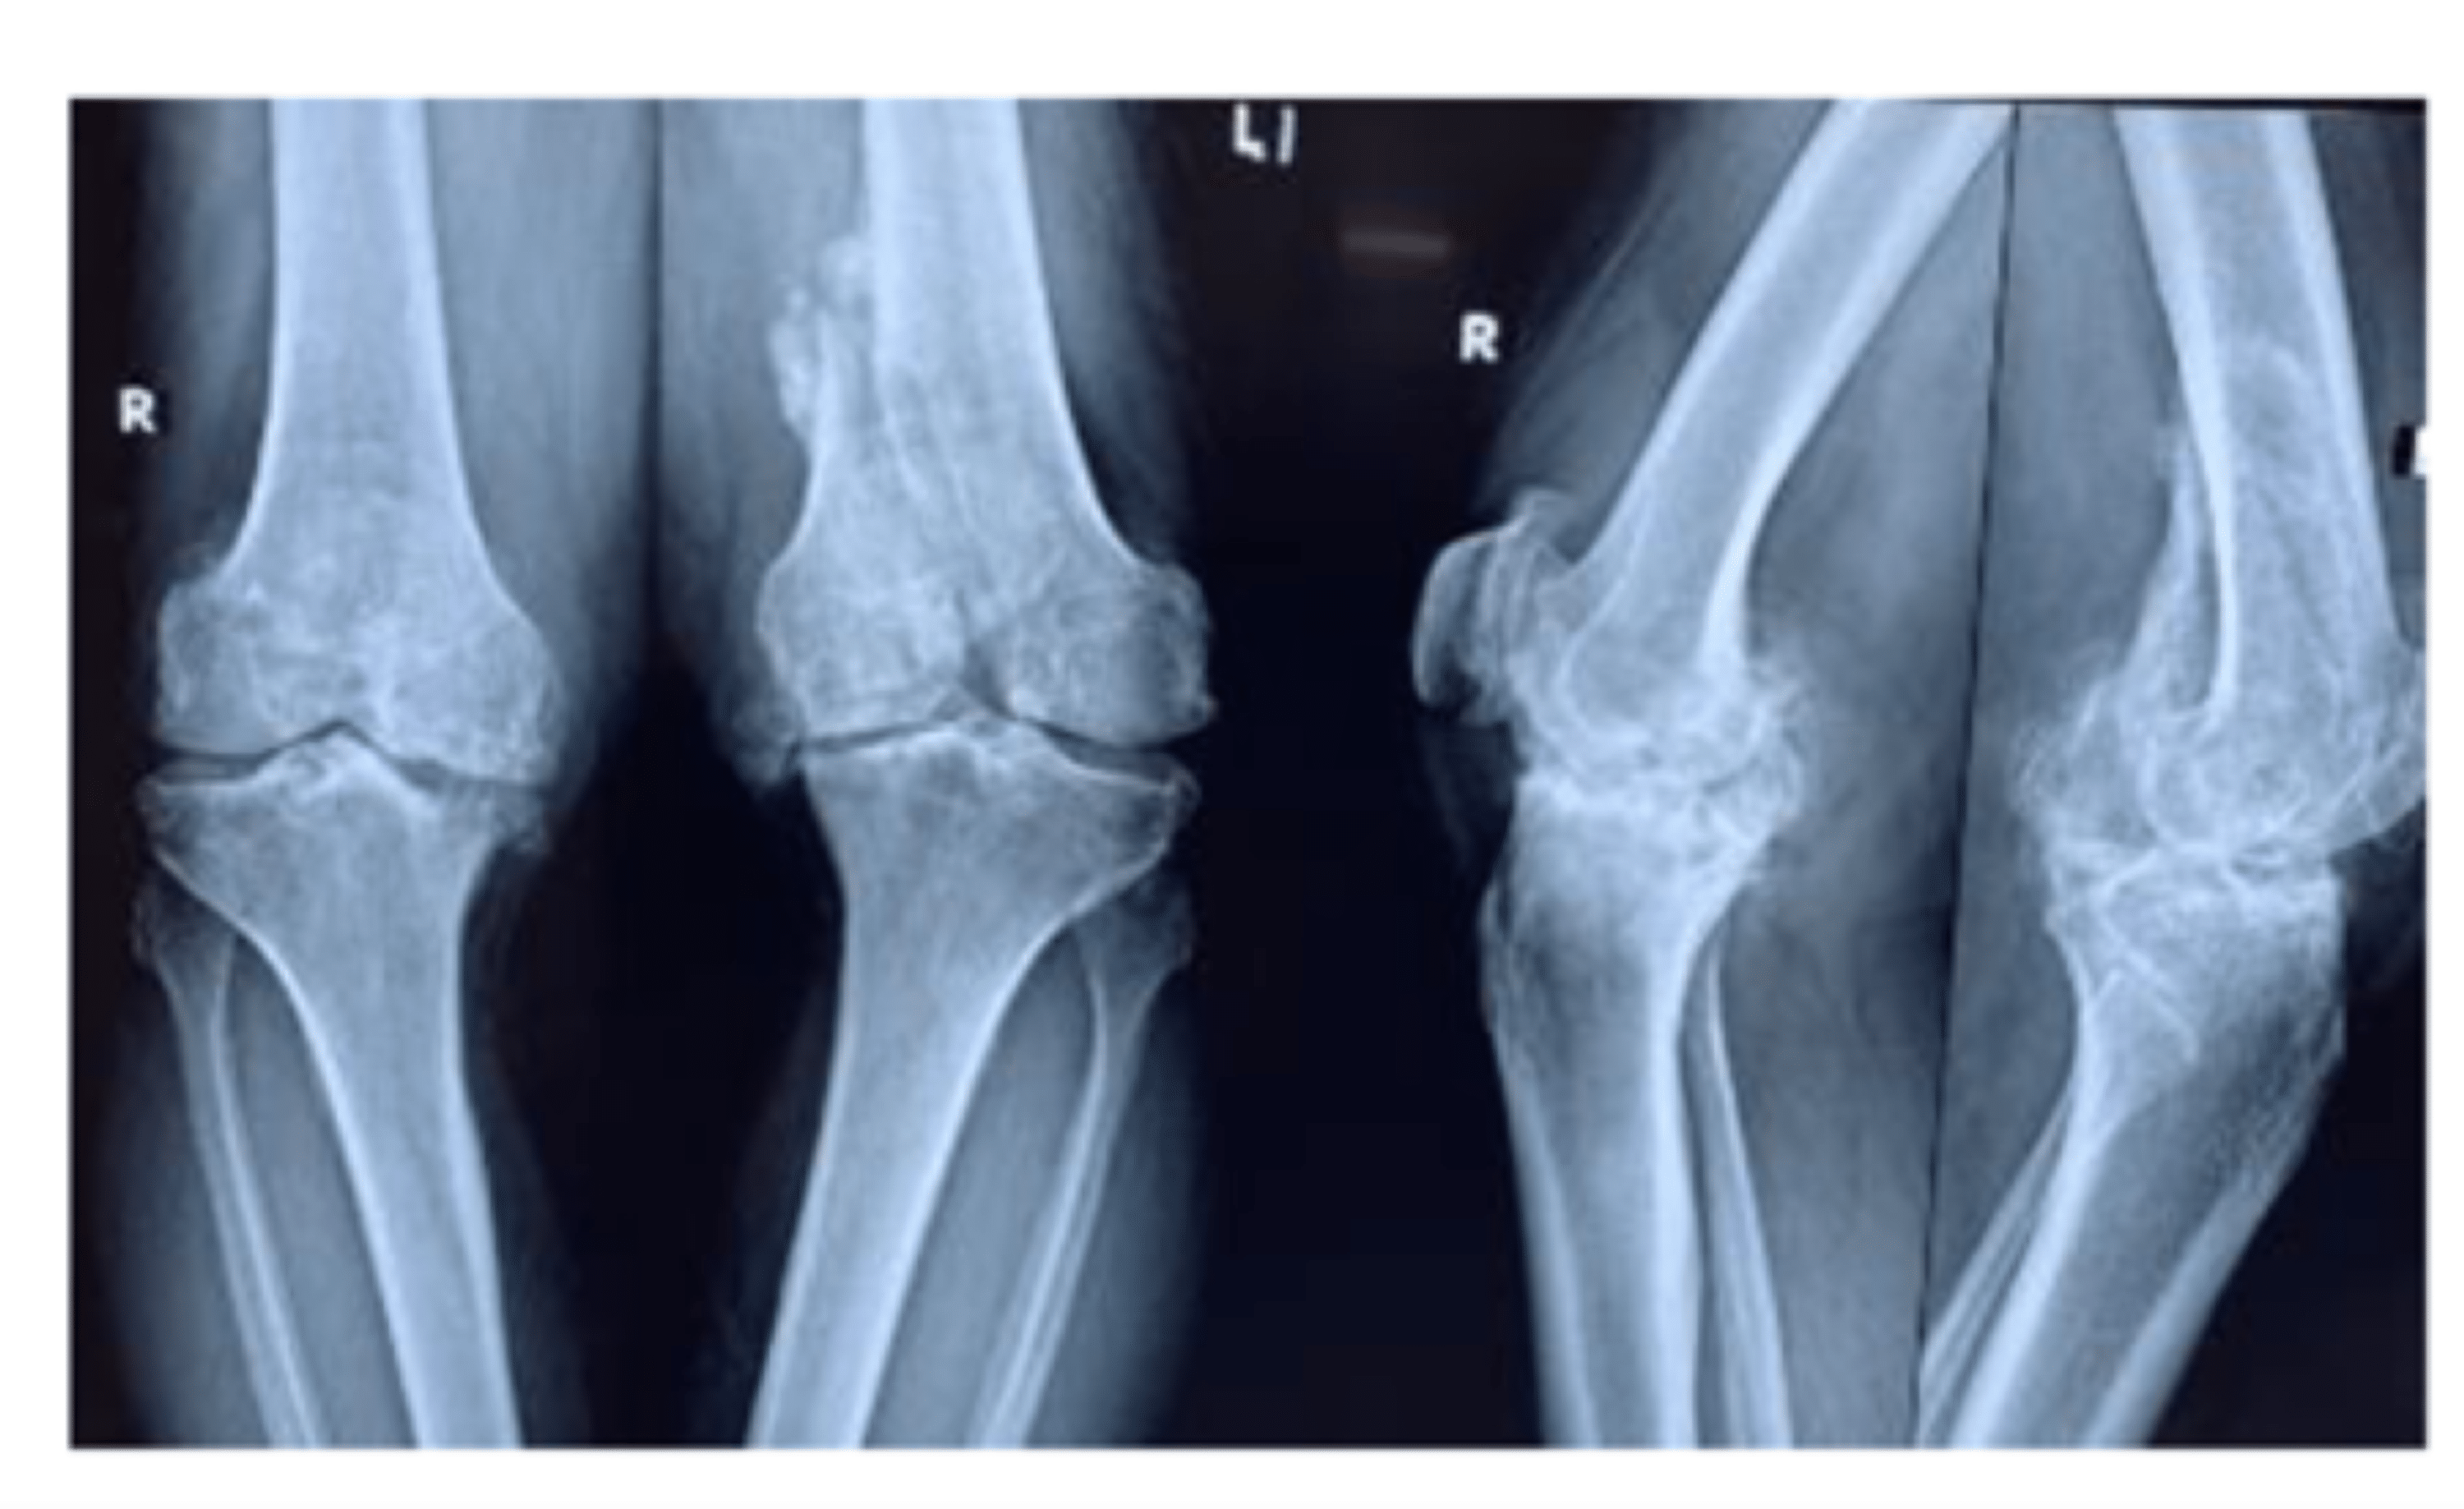

Knee Osteoarthritis Case Report . Oblique (a) and lateral (b) radiographs of the right knee demonstrate advanced tricompartmental. After a physical therapy treatment on the injured knee and a biomechanical study of the position on the bicycle, the symptomatology of the patient's injured knee has improved. Knee osteoarthritis (oa) is a chronic joint disease that can affect all ages, but it is more common in the elderly. Knee osteoarthritis (oa) is a chronic joint disease that can affect all ages, but it is more common in the elderly. This case report describes a total knee arthroplasty (tka) performed for the treatment of a primary knee osteoarthritis.